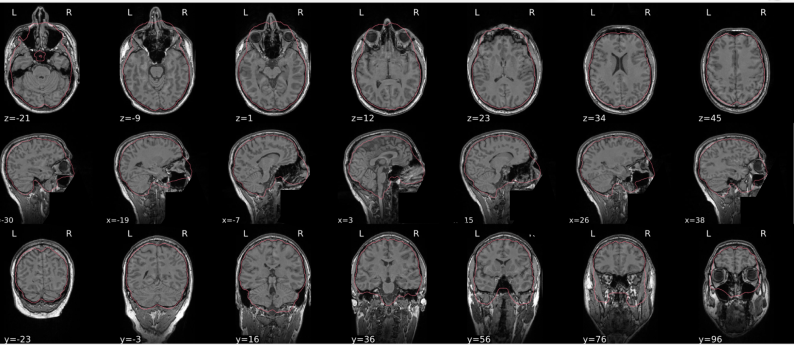

T1w skull stripping

Skull stripping is the process separating the brain (cortex and cerebellum) from the skull. The red line follows the outline of the brain and it separates it from the skull.

Example of a good subject

- There are no skull stripping errors, such as portions of the brain missing, or too much of the skull retained

- The red line follows the outline of the brain

Example of a bad subject

- There are skull stripping errors, such as portions of the brain missing, or too much of the skull retained

- NOTE: check all the images (slices) in the report. If only one image (slice) looks problematic, it is possible that the subject is okay and it is just a visual issue in that particular screenshot

Summary

| Good | Bad |

|---|---|

| The brain is fully inside the red line | Structures like the cranium or the eyes are inside the red line |

| No important brain structures are outside of the red line red line follows the natural outline of the brain | Important brain structures are missing inside of the red line |

-> if only one slice is problematic, it could be an issue related to the visual depiction of the data instead of an issue related to the test subject